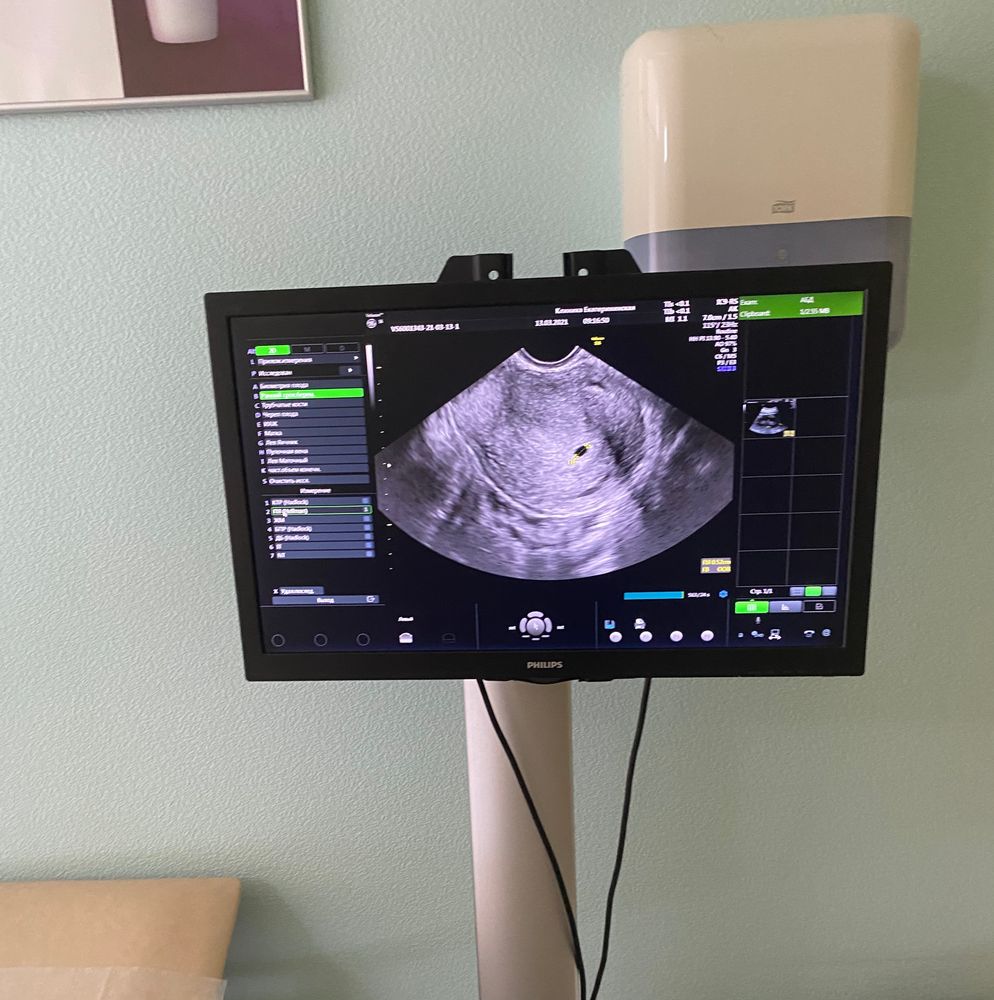

Изображение Вот был хгч как у вас и через денёчек такая картина на узи) а скоро моей точечки уже 2 годика💜🤗

11 числа уже узи можно) точечку посмотреть свою 😍